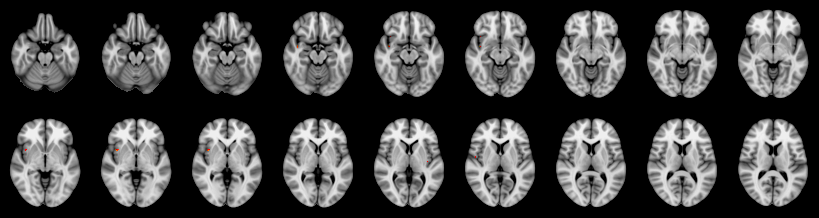

Combined

Tippett:

Fisher:

Stouffer:

Edgington:

Mudholkar–George: